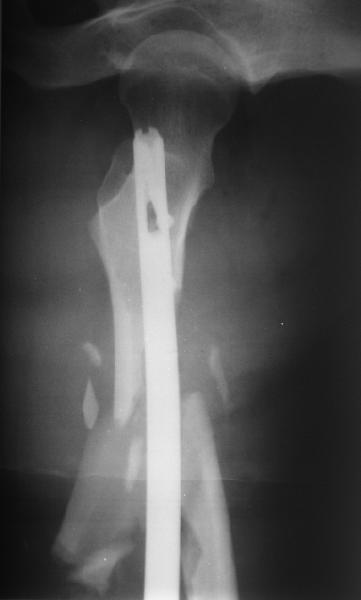

Мы бы не стали открывать, такие переломы срастаются, хотя бы и с краевым дефектом. То есть если удалять стержень потом, то сильно попозже обычного. В приложении пример. Сразу после операции и через 11 мес. Понятное дело, пациент к тому времени давно и не хромал, и функция колена была полная.